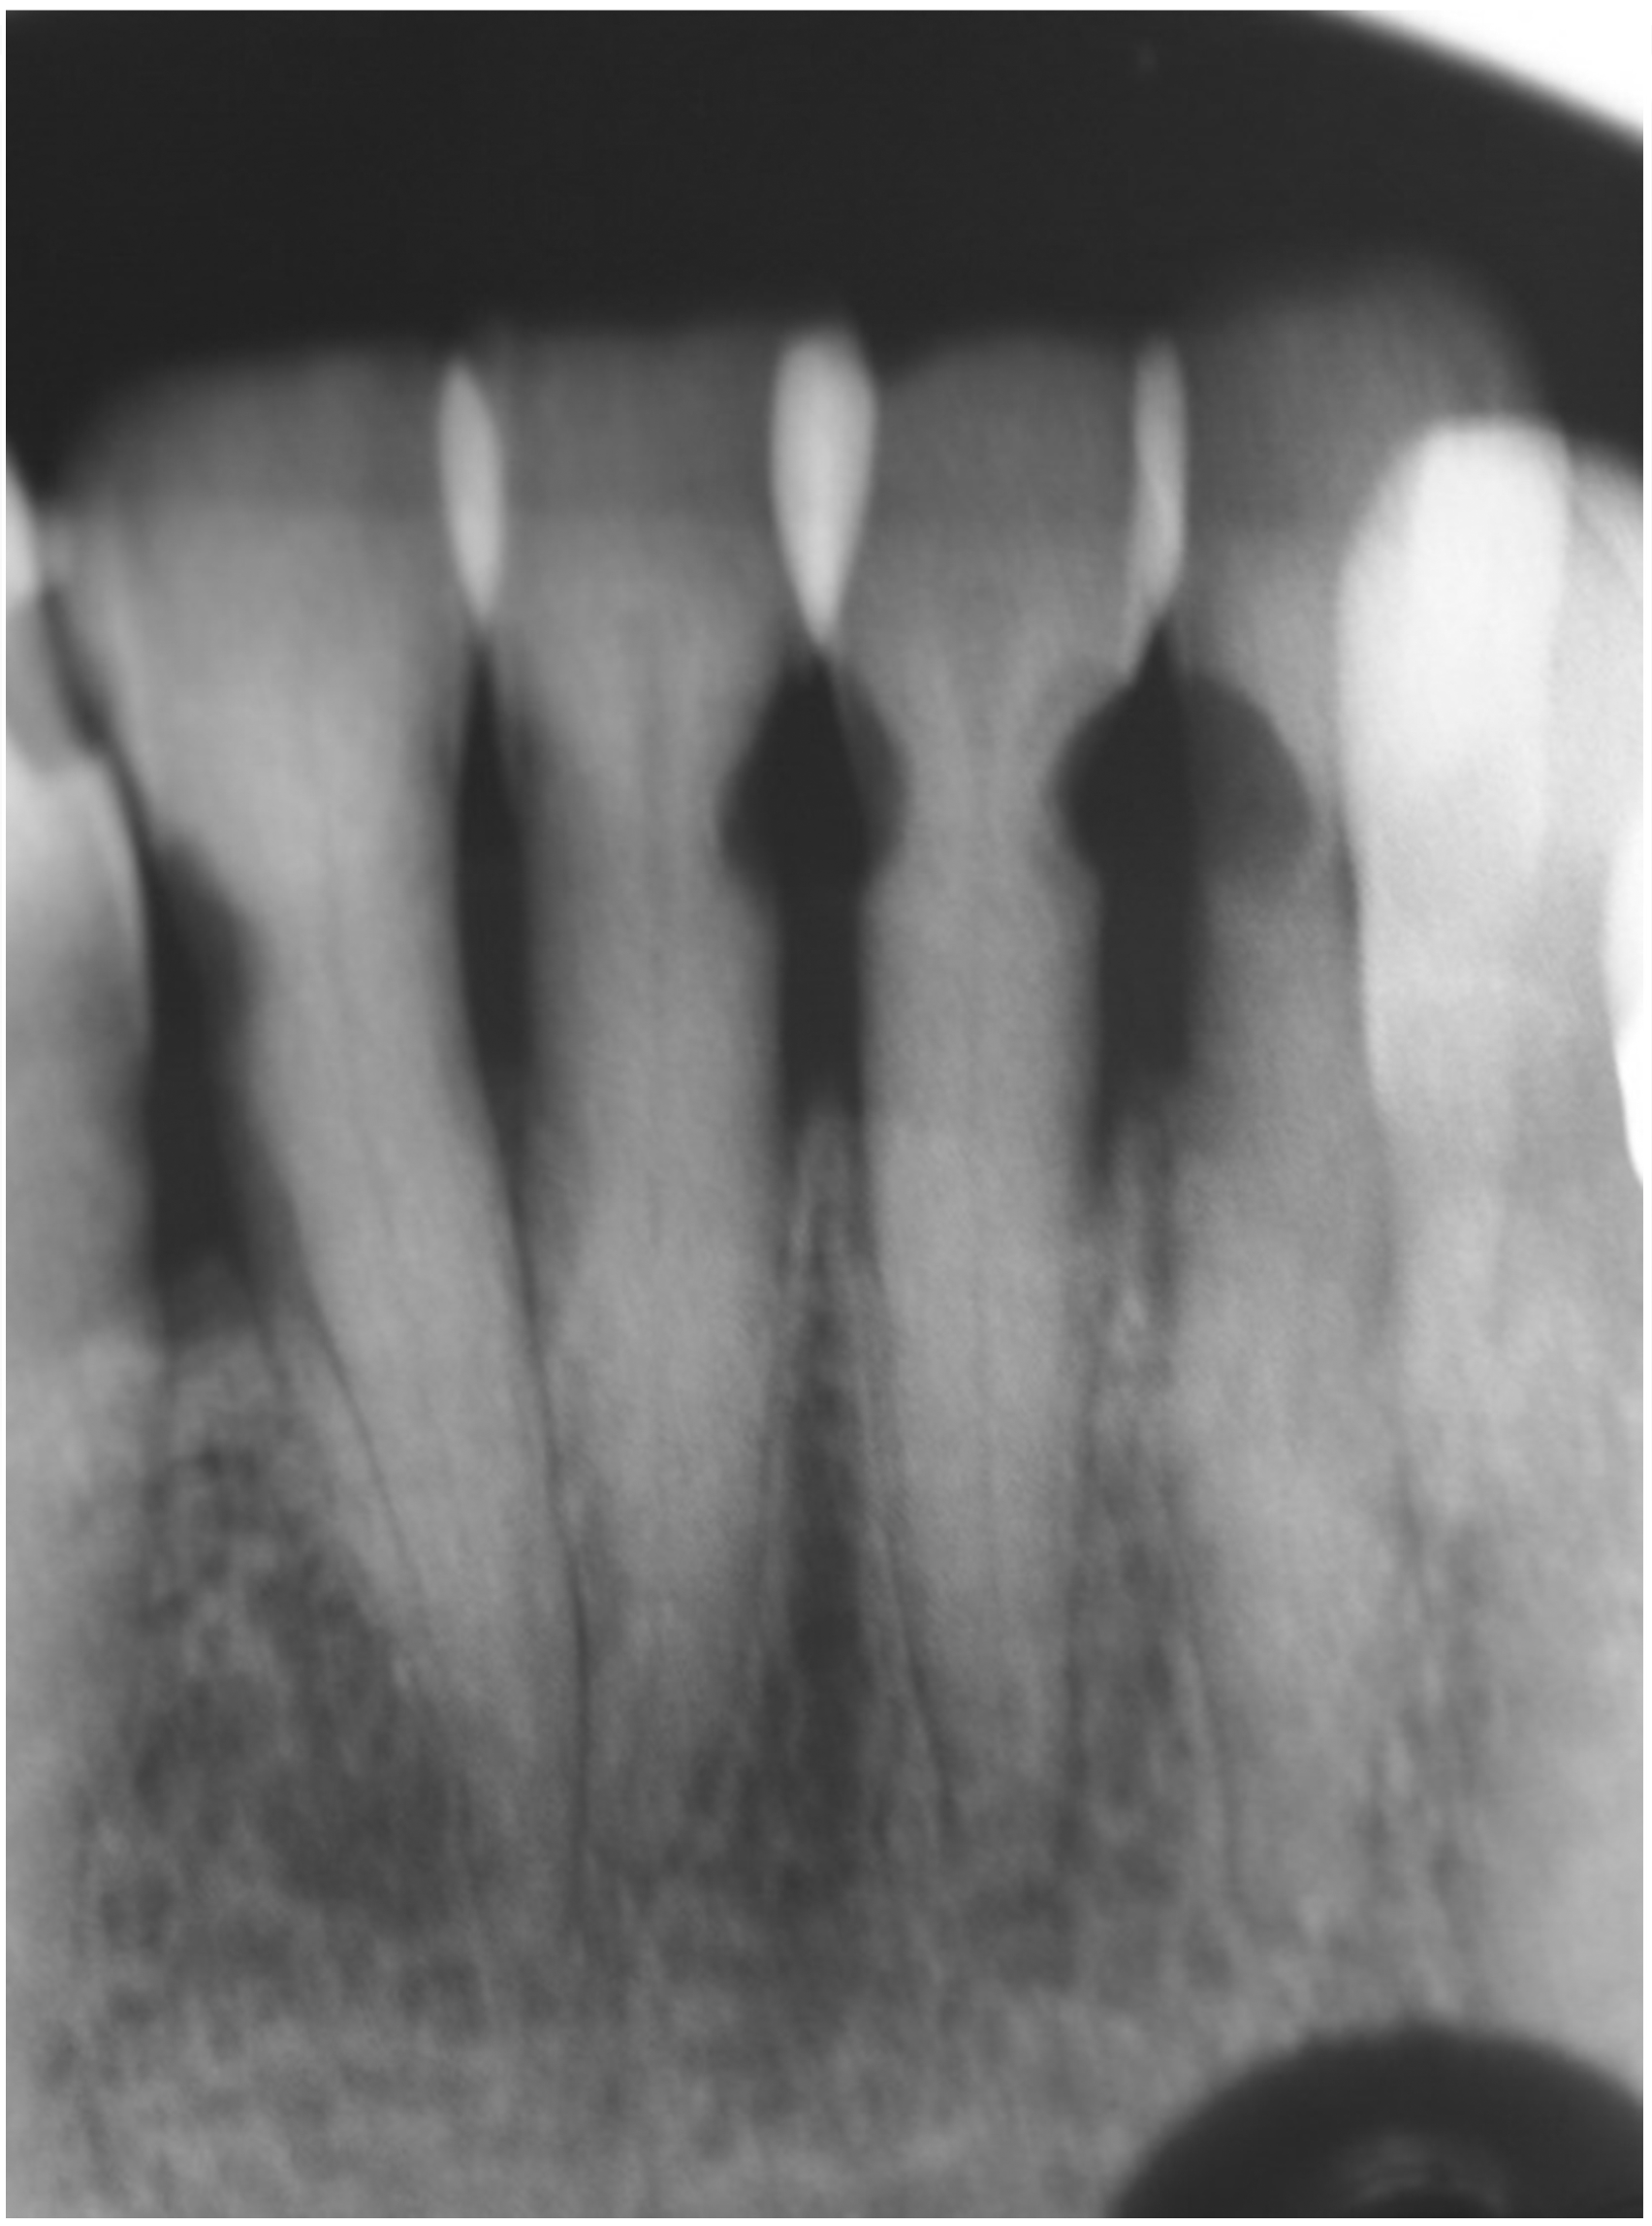

Fig 7. Use of 38% SDF to arrest root caries in permanent teeth of an elderly patient: the lower incisors were responsive to electric pulp testing with no radiographic pathology.

Figure 7